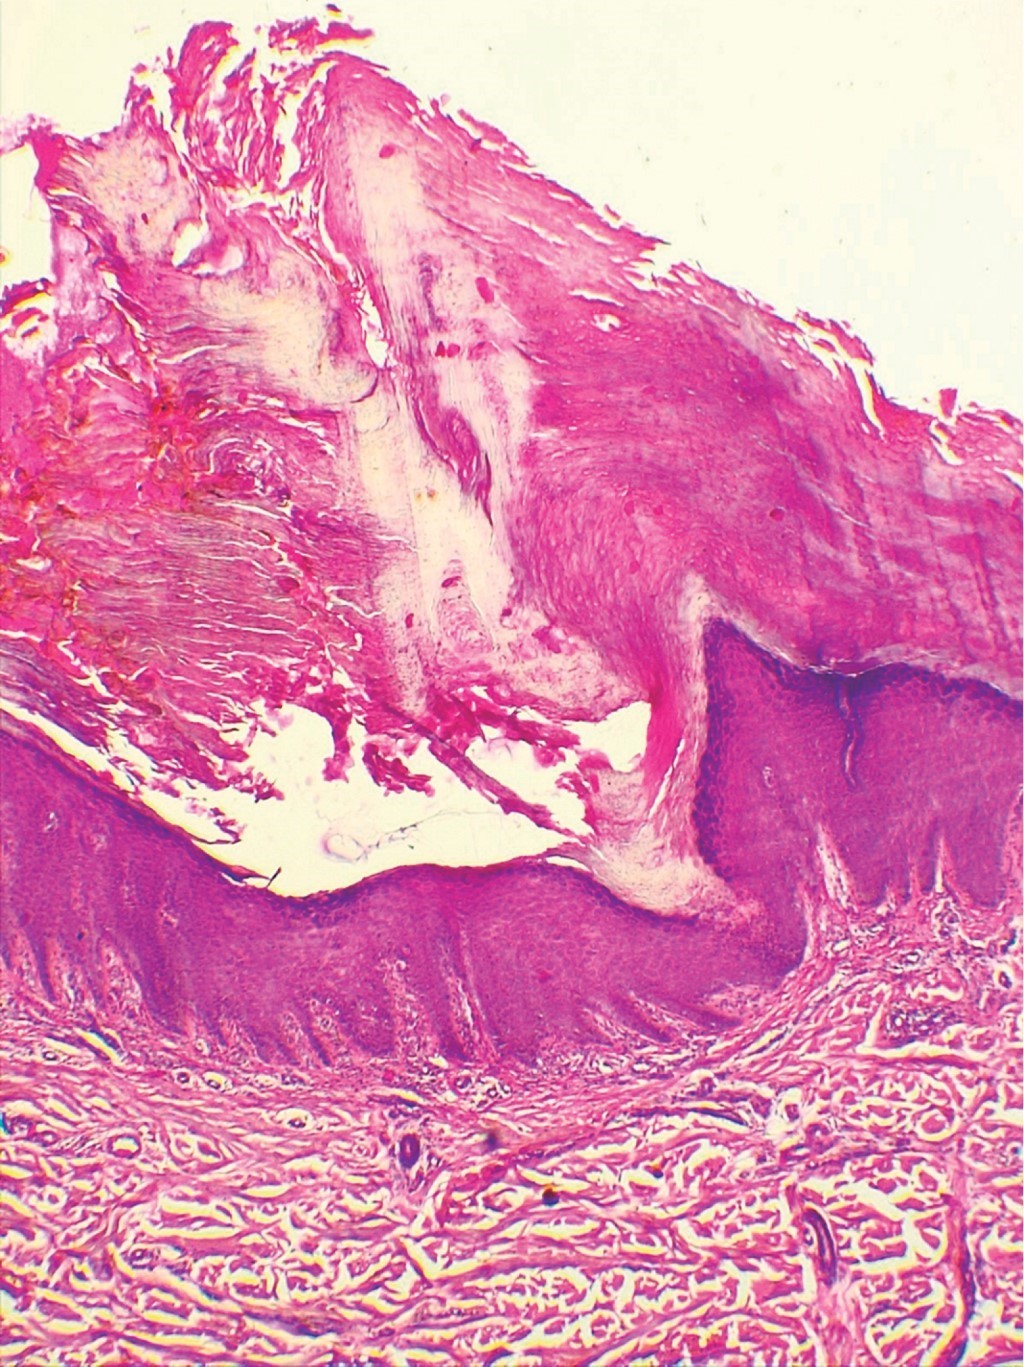

Se realiza estudio histopatológico, cuyas imágenes se muestran en las Figuras 3 y 4.

HISTOPATOLOGíA

Para la toma de biopsia es de suma importancia incluir el borde elevado hiperqueratósico de la lesión. En la PQ de Mibelli, la invaginación se extiende profundamente y se aleja de la porción central. En el centro de dicha zona se eleva una columna paraqueratósica, la laminilla cornoide, que representa el rasgo más característico de la PQ.

Dentro de la columna paraqueratósica, las células se aprecian homogéneas, con núcleos picnóticos. En la epidermis debajo de la columna, los queratinocitos están dispuestos de manera irregular y tienen núcleos picnóticos con edema perinuclear. En la base de la laminilla cornoide, en el estrato espinoso, algunas células muestran citoplasma eosinofílico como resultado de una queratinización prematura, lo cual corresponde a células disqueratósicas. Habitualmente la zona donde surge la columna paraqueratósica carece del estrato granuloso.9